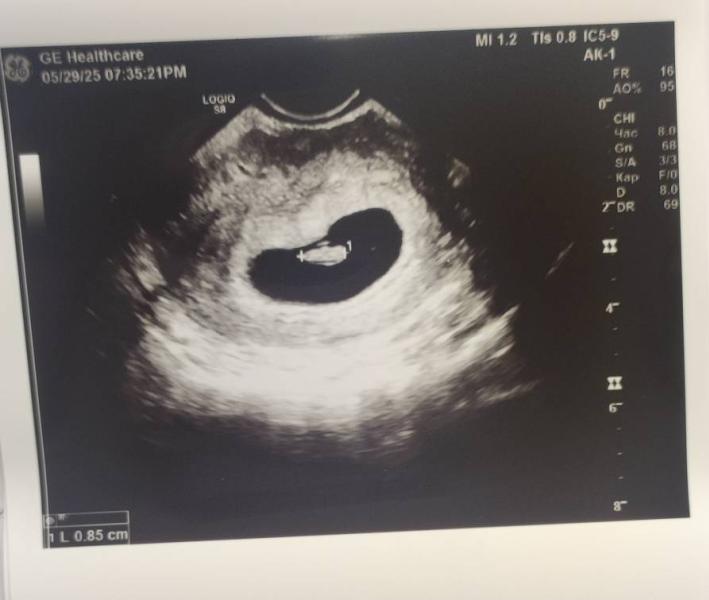

Как растет малыш: от пульсации до четкого сердцебиения за неделю!

Неделю назад была только пульсация.

Сегодня уже четкое сердцебиение 🥰

И подросли за неделю.

Ктр был 2.5мм, сегодня 8.5мм.

Расти, бусинка 🤩